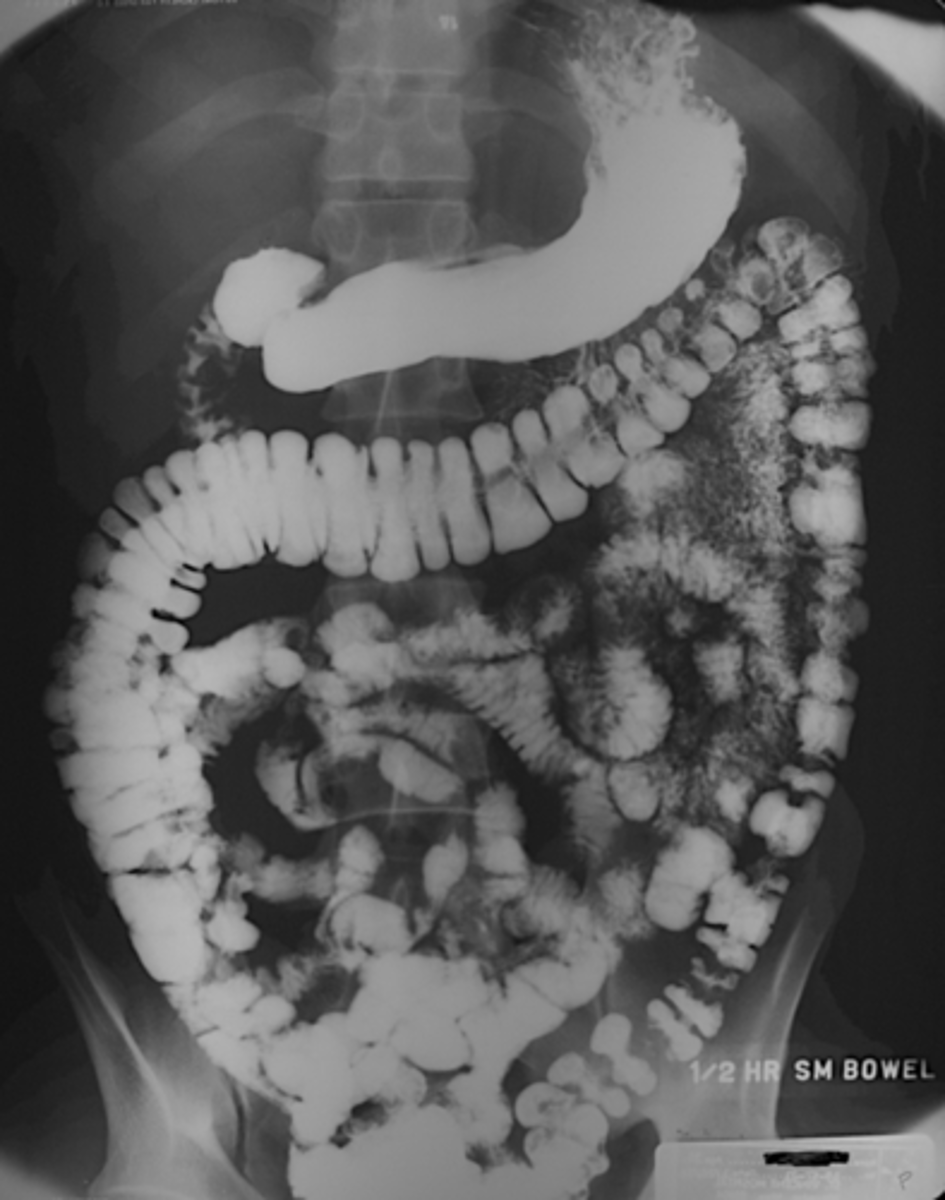

Normal colonic distension (barium enema study)

shows large bowel on barium swallow with fallow through